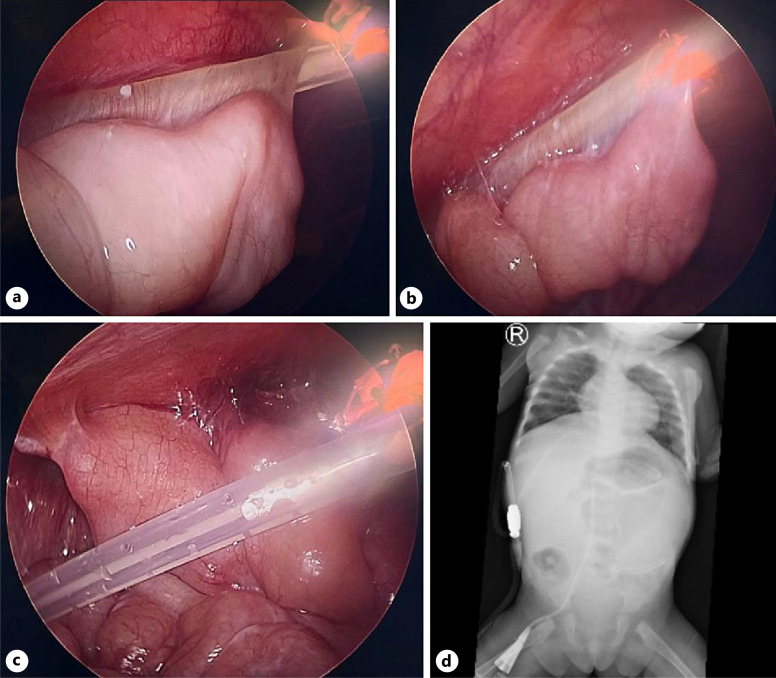

Case presentation: We reported a case of PD catheter adhesion to the ileum in a 1-year-old girl. Previously, the patient underwent laparoscopic insertion of PD catheter due to ESKD. One month after the procedure, there were signs of catheter obstruction. Laparoscopy evaluation and revision were carried out.